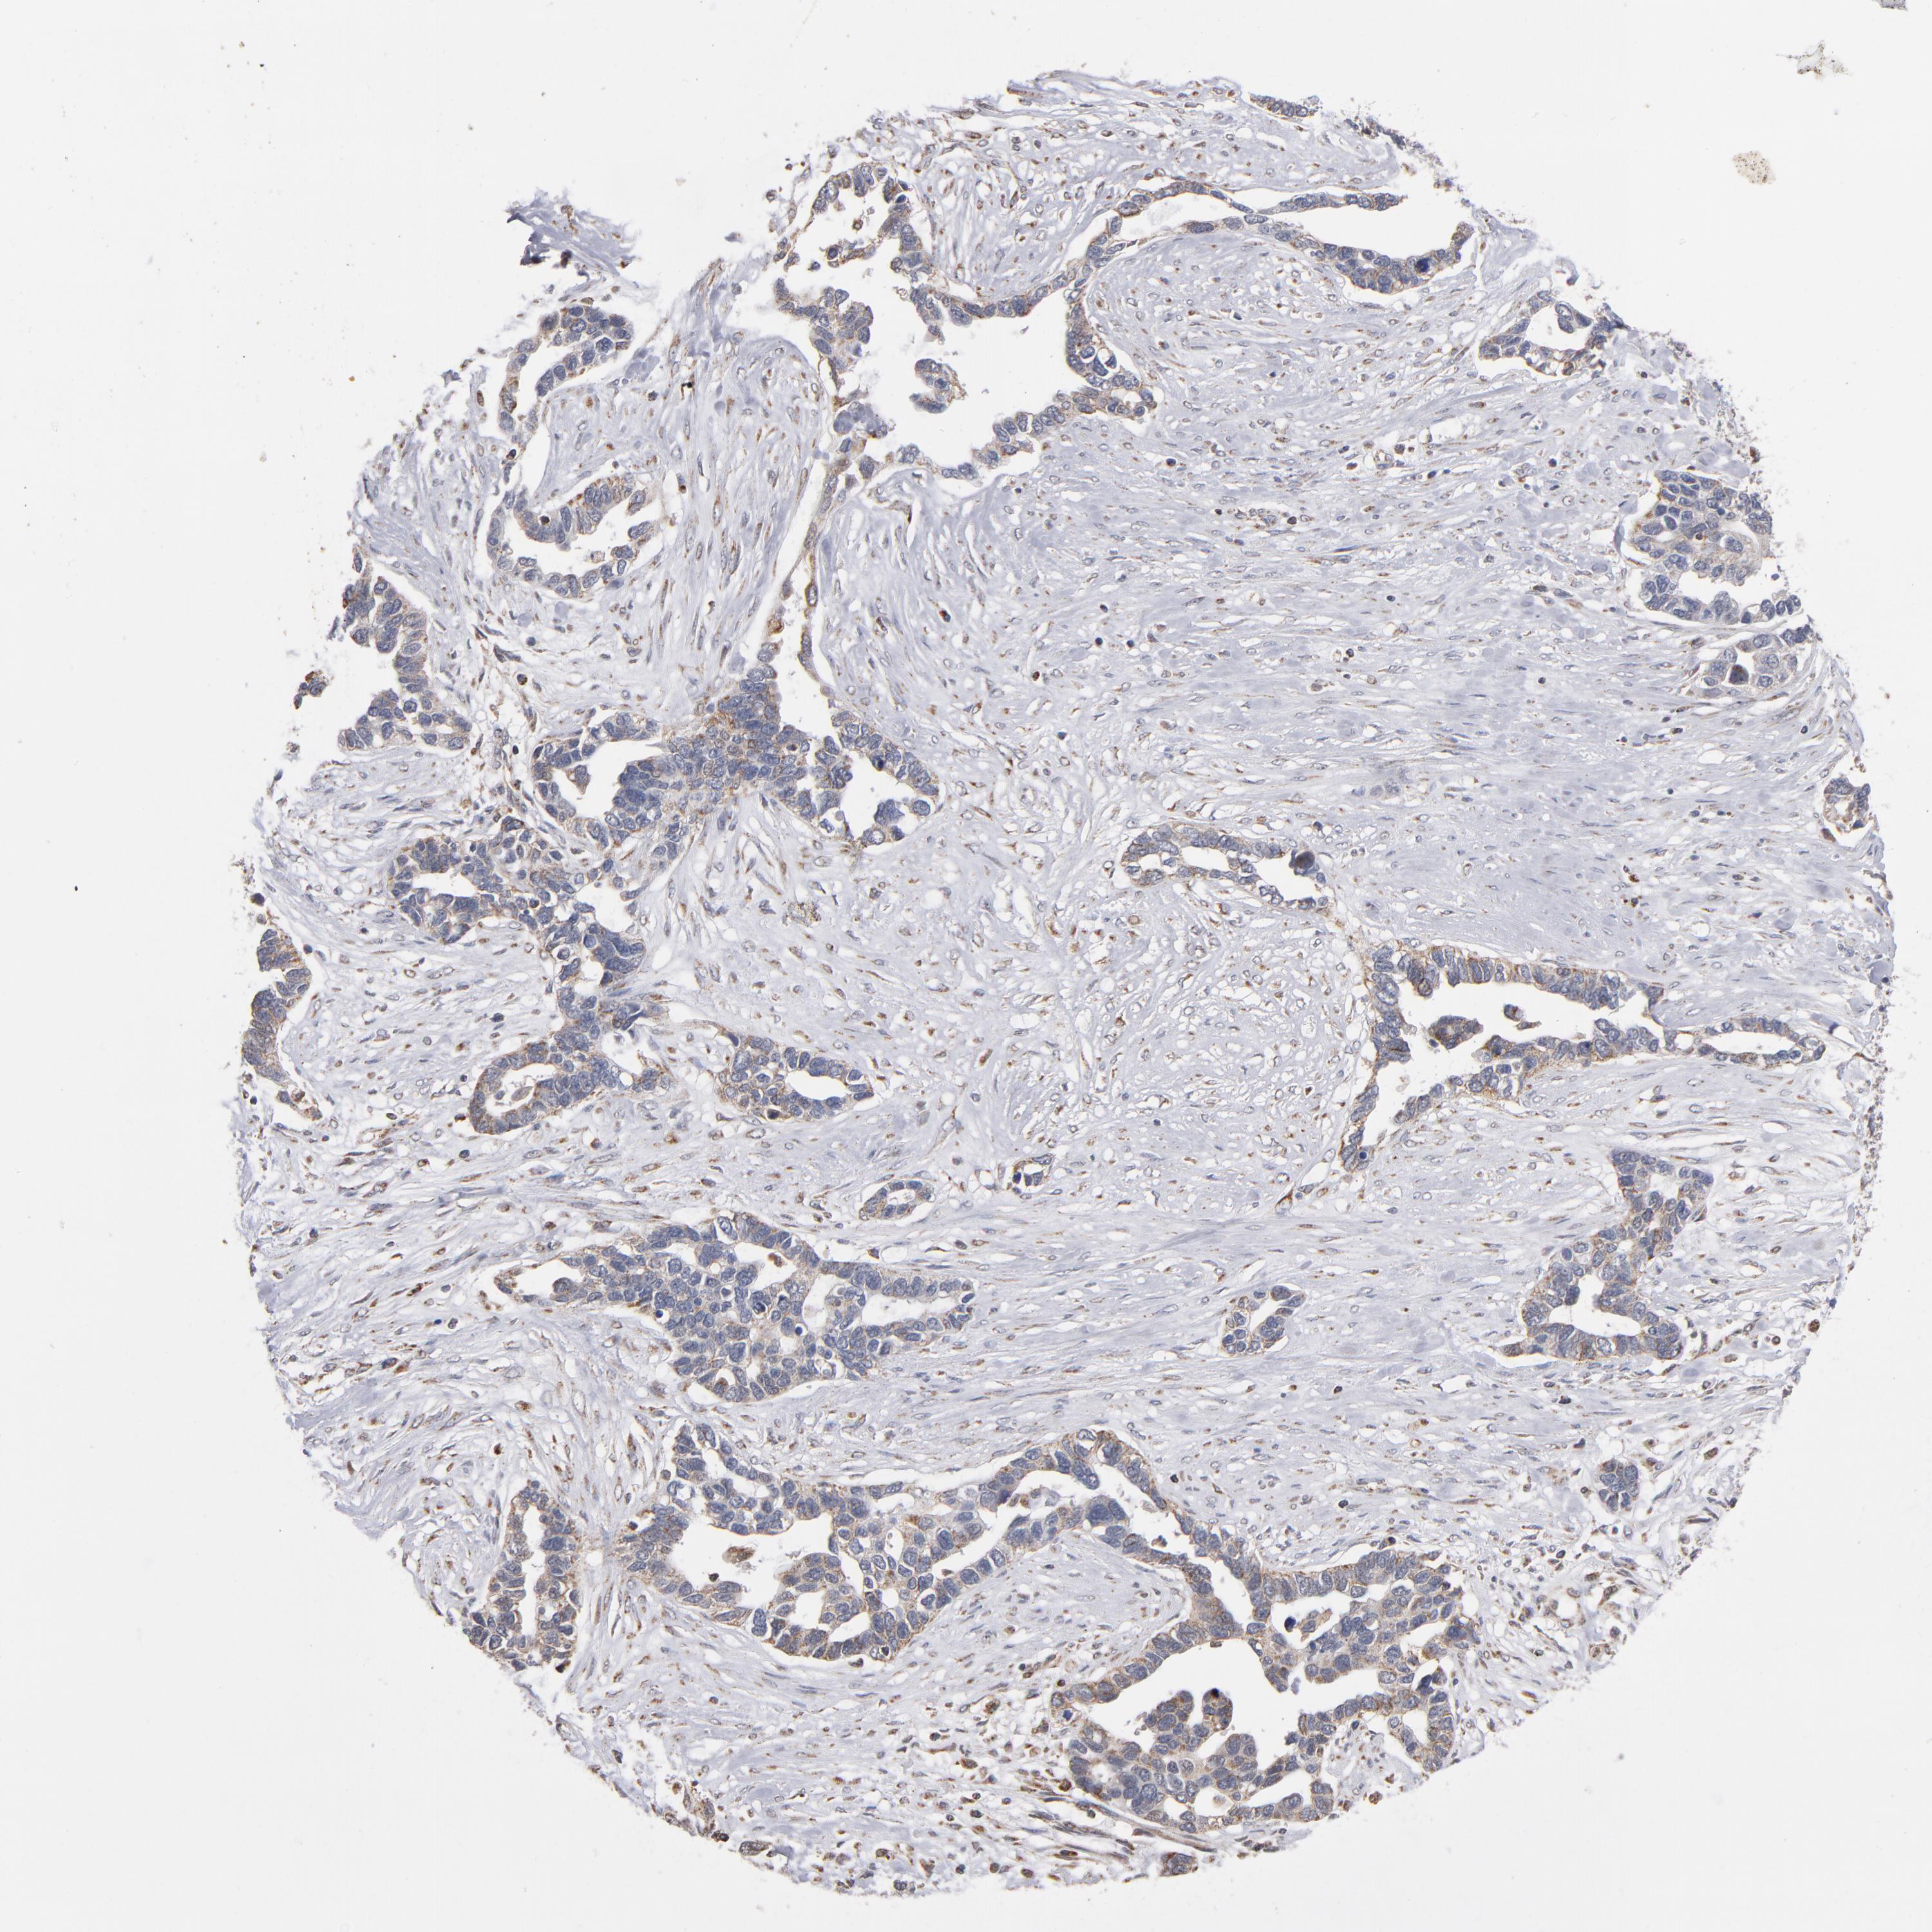

OVARIAN CANCER - Protein expressioni

A mouse-over function shows sample information and annotation data. Click on an image to view it in a full screen mode. Samples can be filtered based on level of antibody staining by selecting one or several of the following categories: high, medium, low and not detected. The assay and annotation is described here.

Note that samples used for immunohistochemistry by the Human Protein Atlas do not correspond to samples in the TCGA dataset.

Antibody stainingi

Antibody staining in the annotated cell types in the current human tissue is reported as not detected, low, medium, or high, based on conventional immunohistochemistry profiling in selected tissues. This score is based on the combination of the staining intensity and fraction of stained cells.

Each image is clickable and will lead to virtual microscopy that enables deeper exploration of all samples and also displays staining intensity scores, fraction scores and subcellular localization as well as patient and tissue information for each sample.

Antibody HPA002893

Staining

High

Medium

Low

Not detected

Intensity

Strong

Moderate

Weak

Negative

Quantity

>75%

75%-25%

<25%

None

Location

Nuclear

Cytoplasmic/membranous

Cytoplasmic/membranous,nuclear

Cystadenocarcinoma, serous, NOS

Cystadenocarcinoma, mucinous, NOS

Carcinoma, endometroid